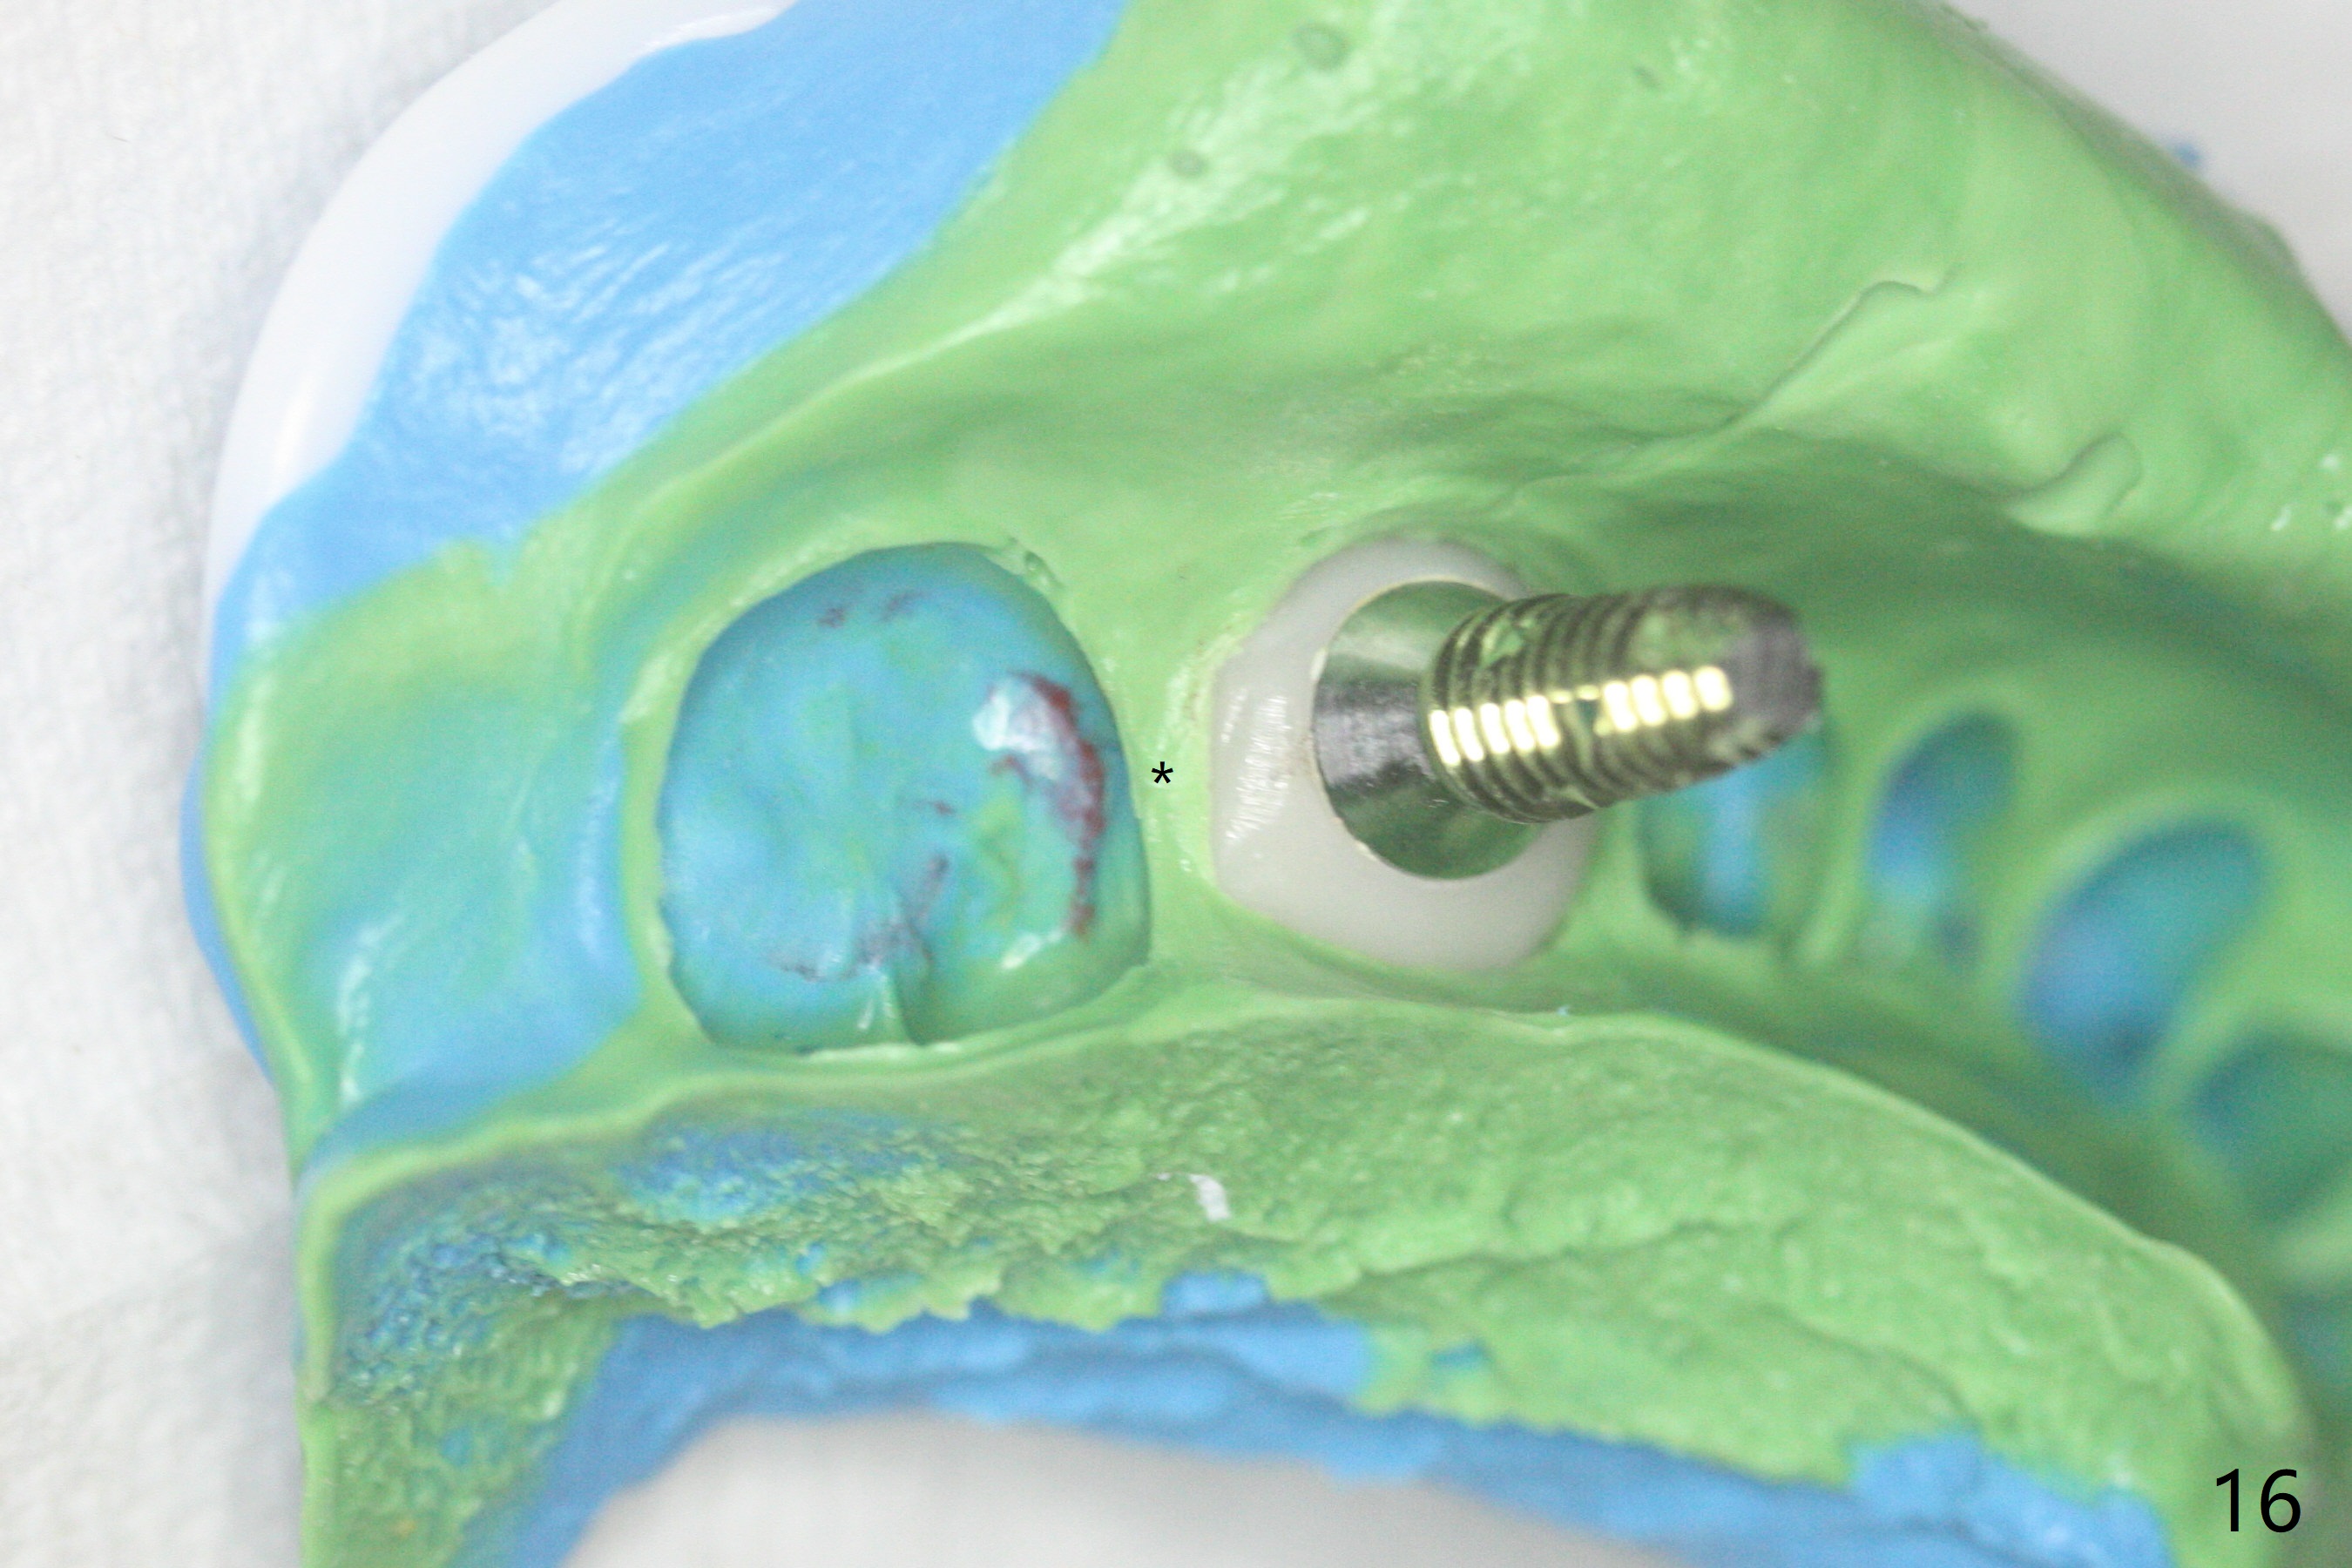

After incision, the ridge at #29 and 30 is found ~ 5 mm wide buccolingually. To place a 4x11 mm IBS implant at #30, the ridge is expanded using BEB technique (bone expansion and bending, Fig.1). It appears that the initial osteotomy at #29 is mesial (Fig.1 yellow dashed line: the distal surface of the root of the tooth #28). After moving the osteotomy distal, the final implant position at #29 (4x11 mm) is within normal limit (Fig.2). The bone at #29 seems to be not so dense that bending (using 1.6 mm drill) is not necessary (using Magic Split and Magic Expanders 3 and 3.8 mm). Later the implant at #30 (4x11 mm) is placed deeper (Fig.3). After placing bone graft around the implants/abutments and suturing, the ridge looks wider with apparent formation of the gingival bands around the abutments (Fig.4 *). Three months and a half postop, bone loss is minimal (Fig.5) and gingival bands forms around the abutments (Fig.6). Fig.7 is taken 1 month post cementation (panoramic X-ray). The patient chews normally 1 year (Fig.8) and nearly 2 years (Fig.9,10) post cementation. The crown at #31 needs recementation 2 years 7 months post #30 cementation; the incomplete seating of the abutment was noted for the first time (Fig.11). Five months later the patient is going to be retired and wants to travel abroad. After approval, the access hole was reopened; articulating paper shows under occlusion of the crown (Fig.12). Since the gap between the abutment and the implant is large, the abutment/crown complex seems to be necessary to be turned (Fig.13 curved arrow). The proximal surfaces of the crown need to be trimmed (straight lines). After turning, the crown sits down with screw tightening; the patient feels pain from the gingival cuff (Fig.14). After turning, the abutment appears to be completely seated (Fig.15). In fact the mesial and distal surfaces of the crown should have clearance from the neighboring teeth (Fig.14) so that pick-up impression is able to hold the crown/abutment complex securely (Fig.16: *). The crown is separated from the abutment after crown repair. They are seated together (loose connection) using the crown as a guide to seat the abutment. BW is taken without the crown. It appears that the abutment remains seated completely (Fig.17). The apical space is equal between #29 and 30 (Fig.17, as compared to Fig.5).